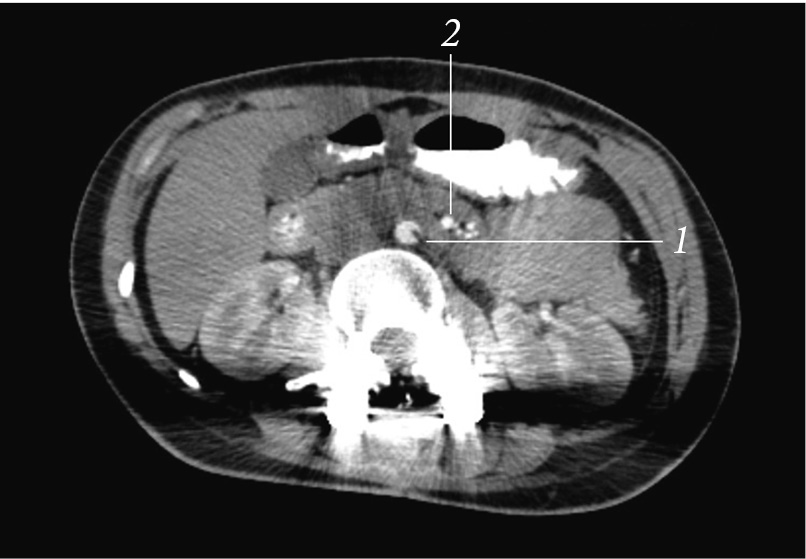

A combined MSCT with contrasting of the gastrointestinal tract and angiography of the abdominal cavity vessels was performed (Fig. 6). In specific, a tube was installed to the level of the duodenum, without distal disturbances in the contrast agent passage. Contrast agent traces in the small and large intestine were found. The stomach was not enlarged, the gas bubble was 110 × 40 mm, and the contents were traces of fluid. When contrasting of the vessels, the aortic–mesenteric angle was 7.7° (normal is 25°–60°), and the aortic–mesenteric distance was 5.1 mm (normal is 10–28 mm), which is a sign of SMA syndrome.

Fig. 6. Combined multispiral computed tomography with contrasting of the gastrointestinal tract and angiography of the vessels of the abdominal cavity: 1 — aorta; 2 — superior mesenteric artery

Conservative therapy was started, which included nutritional support in the form of nutrition through a duodenal probe, inserted with the narrowed part; parenteral nutrition; infusion therapy with electrolyte administration; decompression of the stomach; and prokinetics (metoclopramide). Within 8 days of conservative therapy, a positive trend was noted in the form of relief of vomiting and the appearance of an independent stool. The fluid intake through the mouth (water) with a gradual increase in volume and diet (mashed cereals, mashed potatoes) was started. To increase food tolerance, nutrition was given in small portions, and the body position was changed (on the left side, prone position, and genupectoral position).

For 1.5 months, the patient received conservative therapy, during which complete assimilation of food introduced through the mouth and independent emptying of the intestine were achieved. On the control CT angiography, the aortic–mesenteric angle was 17° (norm 25°–60°), and the aortic–mesenteric distance was 13 mm (norm 10–28 mm) (Fig. 7). However, the patient continued to eat in small portions and experienced discomfort and nausea after eating a large amount of food. To select further treatment approach, monitoring by an abdominal surgeon was recommended to the patient.

Fig. 7. Control computed tomography: 1 — aorta; 2 — superior mesenteric artery